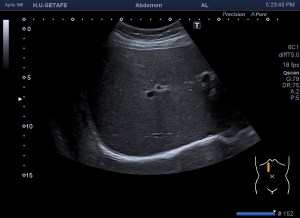

- Vesícula biliar: Visualizada como una estructura en forma de pera, que puede variar en tamaño según la cantidad de bilis que contenga. Su pared aparece como una línea hiperecogénica y suele tener un grosor menor a 3 mm.

- Lumen: Es la cavidad interna de la vesícula biliar donde se almacena la bilis. Se visualiza como una zona anecoica (sin ecos) rodeada por la pared hiperecogénica.